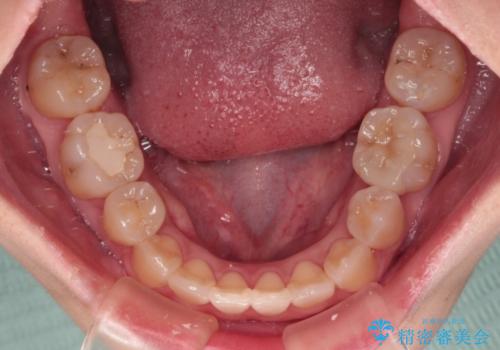

- 奥歯が痛いとのことで来院された患者様です。

上顎親知らず周辺の炎症と、神経組織の失活した歯の炎症による痛みが認められたため、親知らずの抜歯と根管治療を行いました。

根管治療を行った歯はクラウンによる補綴治療が必要となりますが、高校生の頃に行った矯正治療の後戻りも気になるとのことで、補綴治療を行う前に矯正治療を行うこととしました。

後戻りは軽度であり、インビザラインにて歯列を整え、その後にオールセラミッククラウンにて補綴治療を行うこととしました。

ご家庭やお仕事の都合で通院が途絶えた時期があり、治療は長期間となりましたが、無事に終えることができました。